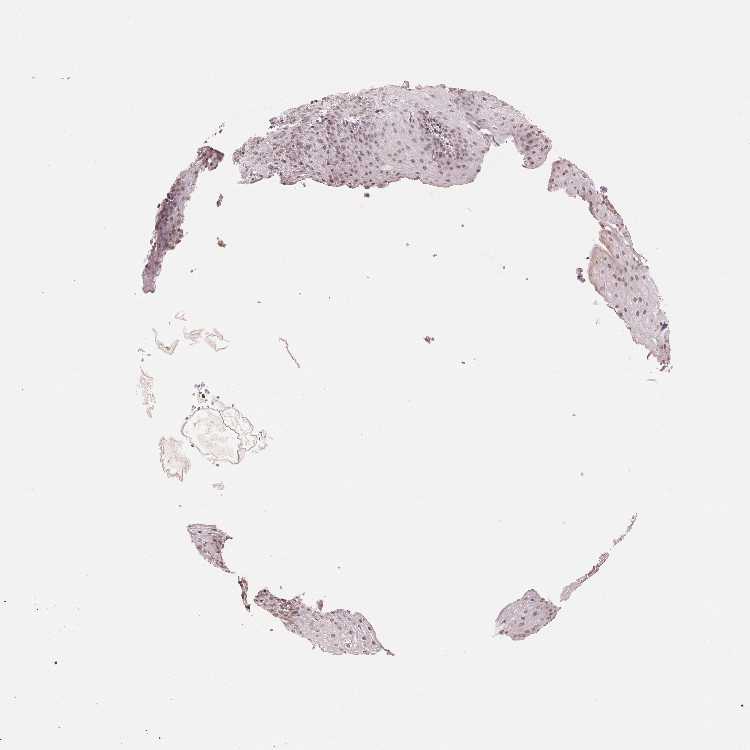

ESOPHAGUS - HPA RNA-seqi

The RNA-seq details section shows detailed information about the individual samples used for the transcript profiling and results of the RNA-seq analysis.

Information about each individual sample is listed below, including gender, age, a tissue section image and estimated fractions of cell types. nTPM (normalized transcripts per million) values give a quantification of the gene abundance which is comparable between different genes and samples.

Female, age 70

Esophagus sample 130

nTPM: 9.9

Cell types%

Squamous epithelial cells:

35

Smooth muscle cells:

15

Skeletal muscle cells:

5

Other cell types:

45